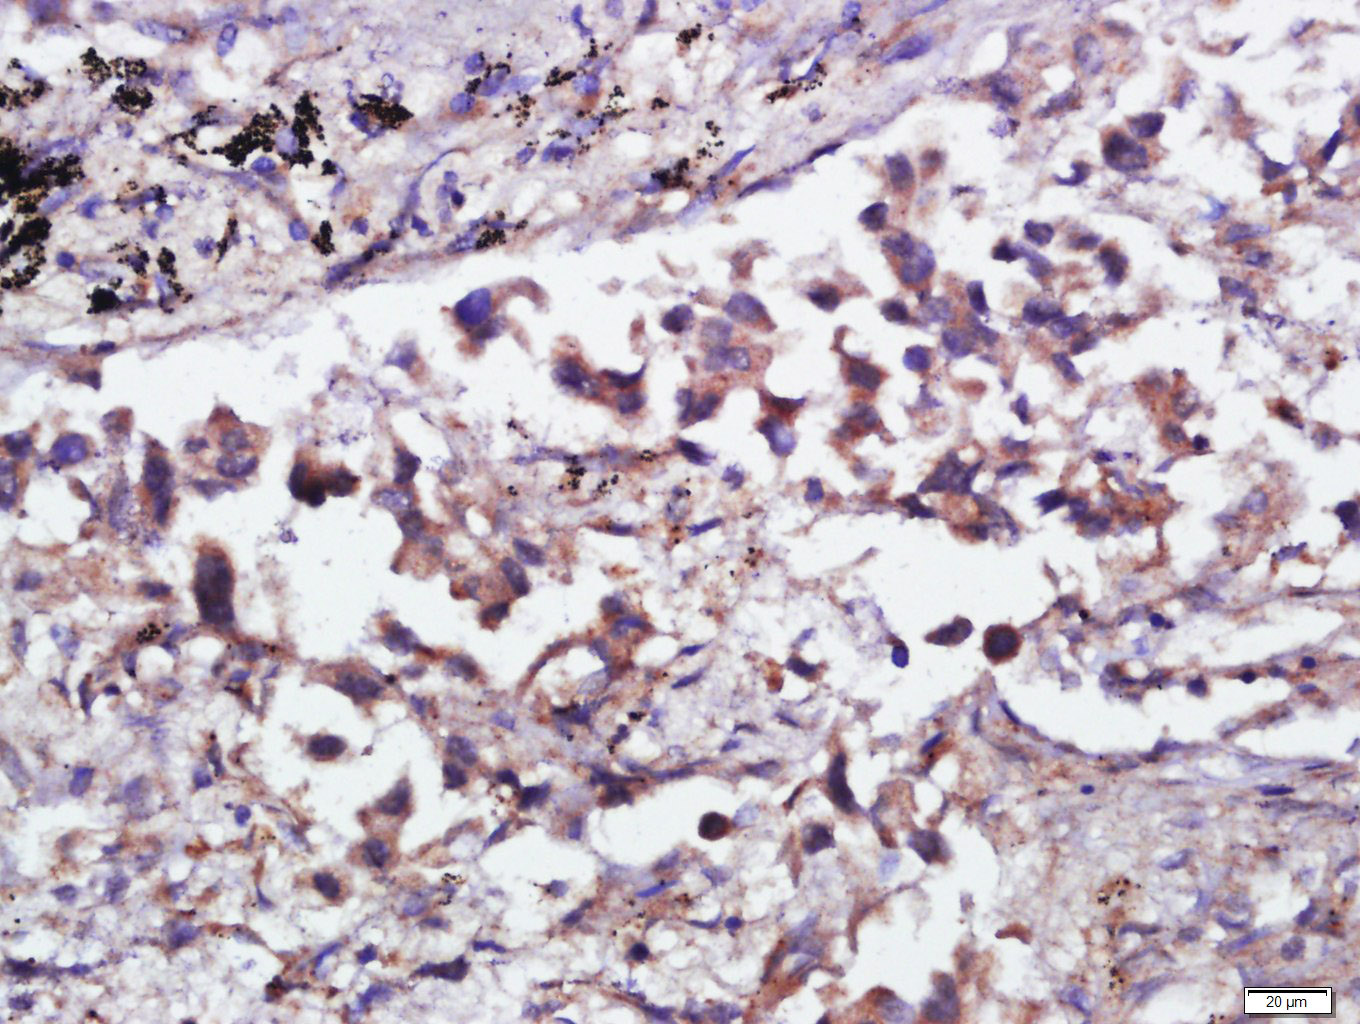

Antigen retrieval: citrate buffer ( 0.01M, pH 6.0 ), Boiling bathing for 15min; Block endogenous peroxidase by 3% Hydrogen peroxide for 30min; Blocking buffer (normal goat serum,C-0005) at 37℃ for 20 min;

Incubation: Anti-CPNE1 Polyclonal Antibody, Unconjugated(bs-14024R) 1:400, overnight at 4°C, followed by conjugation to the secondary antibody(SP-0023) and DAB(C-0010) staining